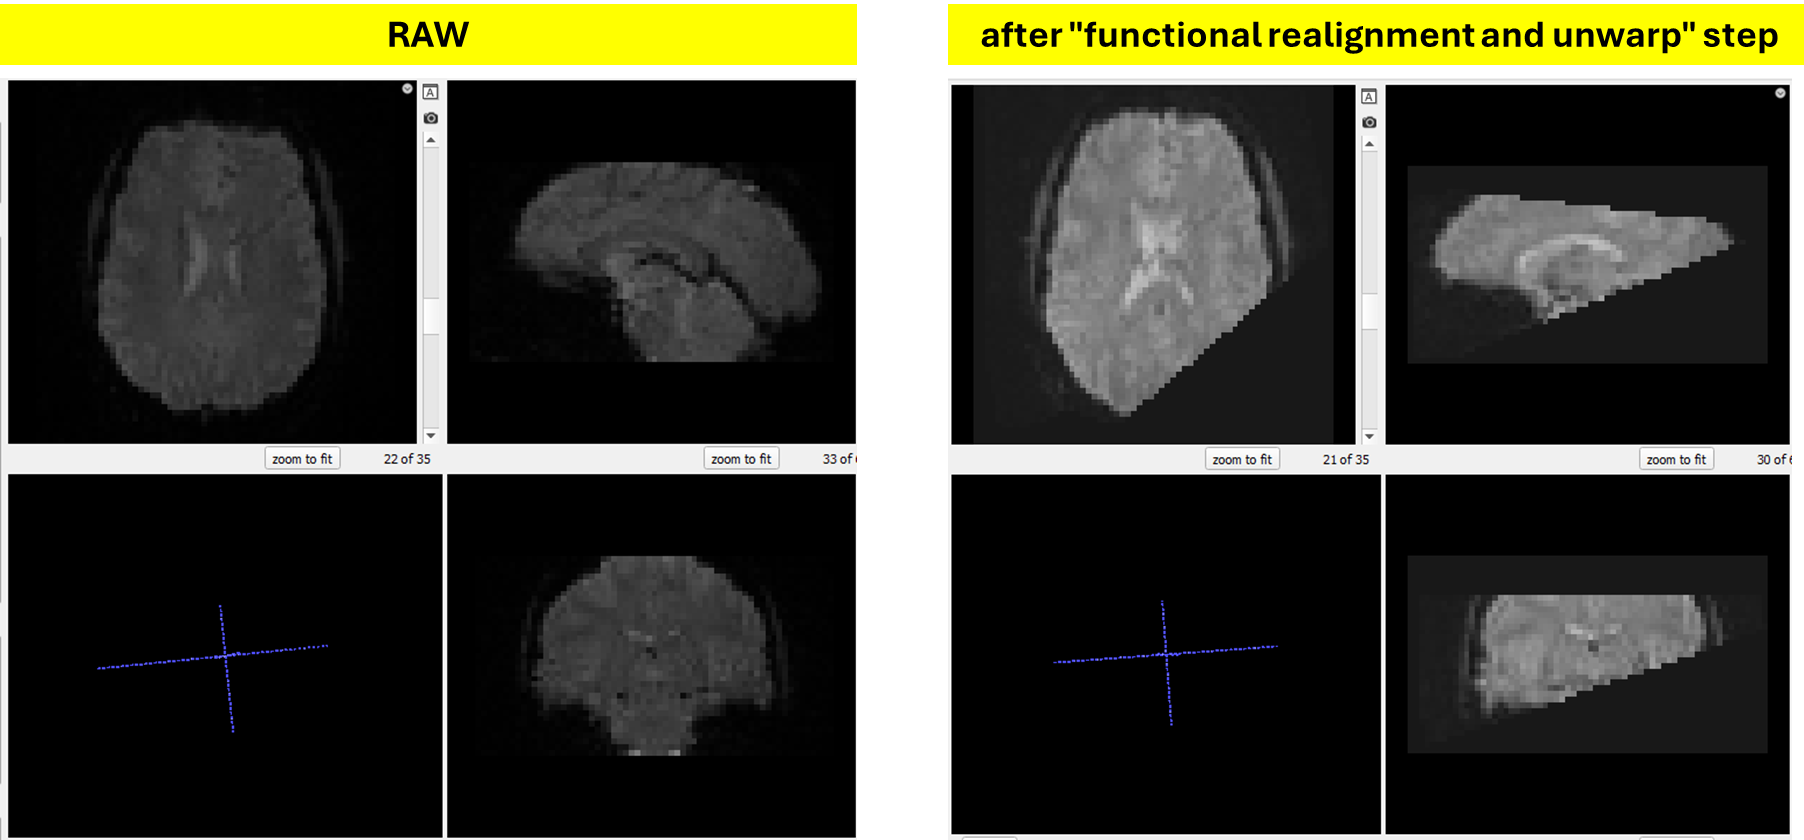

severe cropping of the fMRI data after "Realignment and Unwarp" step

For some participants, the output fMRI data after the “Functional Realignment and Unwarp” step (the u file) shows severe cropping of the volume, as illustrated in the attached image or via this link: https://imgur.com/a/zA1uIPa.